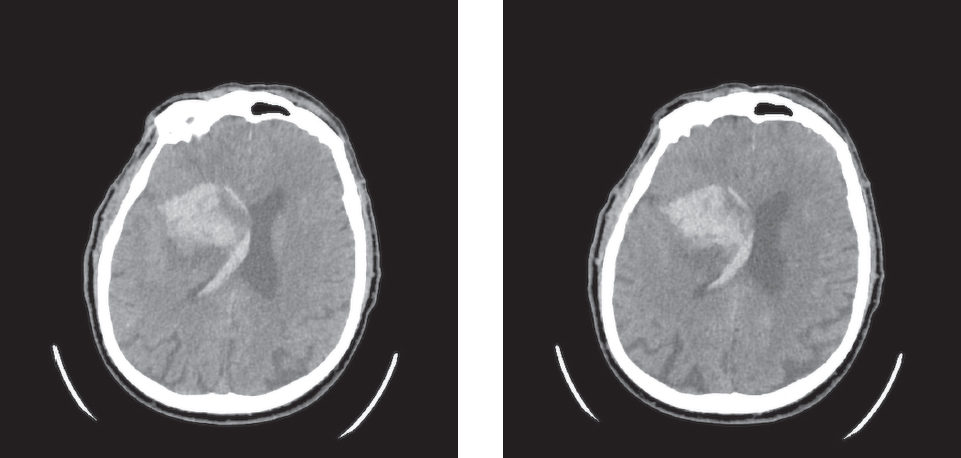

По литературным данным, при мозговых инсультах ОСЭП возникают в 6,3 % случаев (при ишемическом инсульте — 4,2 %, геморрагической трансформации — 12,5 %, внутримозговых кровоизлияниях — 16,2 %). Риск ОСЭП повышают внутримозговое кровоизлияние (отношение шансов (ОШ) 7,2; 95 % доверительный интервал (ДИ) 3,5–14,9); вовлечение коры головного мозга при внутримозговых кровоизлияниях (ОШ 6,0; 95 % ДИ 1,8–20,8) и ишемических инсультах (ОШ 3,1; 95 % ДИ 1,3–7,8); ишемический инсульт с геморрагической трансформацией (ОШ 2,7; 95 % ДИ 0,8–9,6) [3]. Клинический пример — рис. 1.

Рис. 1. Компьютерная томография головы. В базальных ядрах правого полушария визуализируется зона ишемических изменений (размерами 5,2 × 4,9 см) с наличием зоны гиперденсных (геморрагических) изменений (плотностью +60HU – кровь), занимающей более 30 % зоны ишемии, с прорывом крови в правый боковой, III, IV и левый боковой (небольшое количество в области тела и заднего рога) желудочки. Небольшое количество крови в бороздах теменной области с обеих сторон. Пациент Д., 72 года, госпитализирован в неврологический стационар ввиду внезапно развившейся слабости в левой руке и ноге. При осмотре неврологом, по результатам компьютерной томографии головы диагностировано острое нарушение мозгового кровообращения по ишемическому типу кардиоэмболического генеза в бассейне правой средней мозговой артерии (тромбоз М1 сегмента). Проведена системная тромболитическая терапия, локальная эндоваскулярная трансартериальная тромбэкстракция из сегмента М1 правой средней мозговой артерии и сегмента А2 правой передней мозговой артерии. В первые сутки после дебюта инсульта у пациента развился однократный билатеральный тонико-клонический приступ. По результатам компьютерной томографии головы — геморрагическая трансформация (паренхиматозная гематома 2-го типа — внутримозговая гематома в базальных ядрах правого полушария с прорывом крови в вентрикулярную систему, субарахноидальное кровоизлияние)